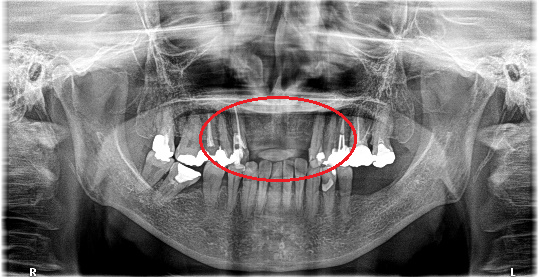

レントゲンで詳しく診てみると、虫歯が歯根のほうまで進行し、保存することができないことがわかり、抜歯しました。抜歯後、骨が大きく欠損していましたので、骨造成を行いインプラントを2本埋入しました。

所感

抜歯後の欠損したところを補う方法には、部分入れ歯、ブリッジ、インプラントがあることを説明したところ、自分の歯と同じような感覚で嚙むことができるインプラントを選択されました。この方は、2016年に右下にインプラント治療をし、インプラントの良さを十分に理解しておられましたので、今回も2本歯を失ったところにインプラント治療を希望されました。今回もX-Guideを使った埋入で、安心安全に行うことできました。

Before

【抜歯後】

After